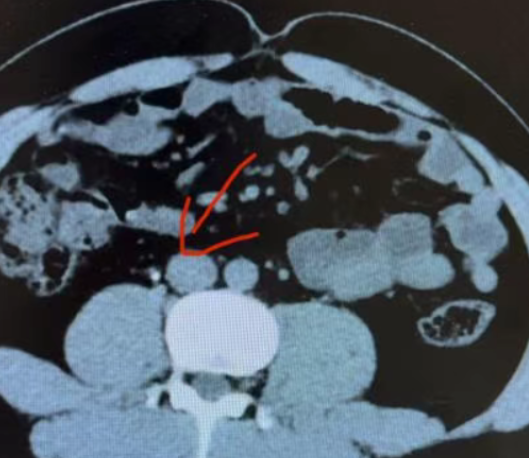

通过B超、CT扫描这些检查手段,能清晰看到这些肿块和正常组织的区别。绝大多数结节都是良性的,很少会变成癌症。医学统计显示,真正需要治疗的恶性结节比例非常低。

目前最常用且最可靠的方法是甲状腺细针穿刺活检,一般是在超声图像引导下,用细针穿刺,抽出一些细胞,由病理专家分析抽出的细胞形态和分化度,确诊结节是良性还是恶性的。截止目前,全世界有超过10万例的甲状腺穿刺病例,超声引导下的细针穿刺没有明显的疼痛,一般也不会引起穿刺针眼的种植转移,大家不用担心。PET-CT是另一种有效的检查方法,可以通过检测细胞的活跃度的影像显示来确定是否为恶性,缺点是检查费用较高,所以并未普及。

甲状腺超声检查不仅可以明确结节的部位、数目、大小、囊性还是实性、结节边缘是否清楚、结节内有无血管斑和微钙化等,还能辅助确诊甲状腺恶性肿瘤,如低回声、血运丰富、微钙化、形态不规则、淋巴结肿大。目前,高分辨的超声是甲状腺结节的首选检查。

有些医生会建议患者接受甲状腺核素扫描,目的是更准确的评估结节是否具备分泌功能。

当患者接受本项检查时,需要仰卧平躺在带有电脑屏幕和电子检测仪的检查床上,医生将放射性核素标记物通过患者手臂的静脉注入到血液中,随后,医生会在电脑屏幕上观察到甲状腺结节的情况,而且整个过程患者不会有痛苦的感觉。

甲状腺核素扫描的缺点:不能准确检测结节的良恶性。